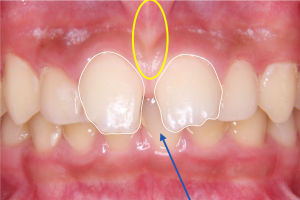

※初診時口腔内写真正面

青色の矢印で示している部分を見ると、歯と歯の間にすき間がある状態であることがわかります。

白い線で上の前歯の形をなぞってみると、歯の大きさや形のバランスに乱れがあることが確認できます。

また、黄色い丸で囲んだ部分には、**上唇の内側と歯ぐきをつなぐヒダ(上唇小帯)**が見られます。このヒダが発達している場合、上の前歯の間にすき間ができやすくなることがあります。